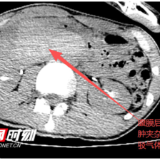

入院时腹部CT。

术中经急诊剖腹探查发现,李明腹膜后形成巨大血肿,十二指肠降部及水平部完全损伤破裂,胰头部挫伤严重,消化液腐蚀周围脏器引发炎症与水肿,腹膜后积血,小肠血管及相邻血管分界不清,使病情变得异常棘手。